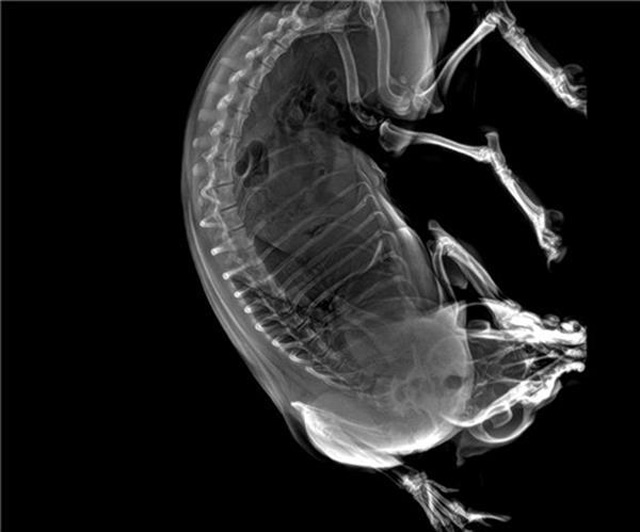

寵物DR的工作原理是X光線穿透動物體后在屏幕或者膠片上面顯示體內影像。輔助寵物醫(yī)生讀片跟準確的治療,寵物DR顯示是寵物醫(yī)院診所的配置,提高了診斷的效率。DR的檢測效率比X線高44%,成像快采集時間10MS以下。3秒左右就可以看到檢查圖像。常規(guī)的胸部DR還要幾分鐘。所以寵物DR的出片速度是非??斓?。很高的空間分辨率低噪音??梢垣@得高清圖像,提高檢測正確率避免誤診等等問題。數字化圖像的優(yōu)勢是可以保留原始數據,圖片識別,二三維的重建,醫(yī)學影像學實現全數字化和無膠片化鋪平了道路。提供照片打印服務,防止照片丟失而重復照片。有針對性的對圖像進行處理,以提高診斷率。寵物DR的輻射量很低的,對人體的輻射風險不大。